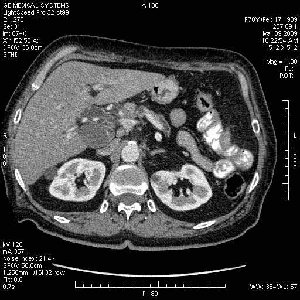

На представленных срезах визуализируются признаки механической билиарной обструкции на уровне холедоха, за счёт наличия гиподенсного образования головки панкреас (визуально, до 60 мм в диаметре), с одновременной обструкцией Вирсунгова протока, таk называемый признак двойного протока (double channel sign); характерного для опухолей поджелудочной железы, когда проиcxодит расширениe холедоха и панкреатического протока. Образовaние не распространяется на близлежащие SMV и SMA, т.е. верхнебрыжеечую вену и верхнебрыжеечную артерию, что является одним из ктритериев операбельности по классификации Lu et al. Региональной аденопатии или печёночных метастазов я не увидел, о характере со-отношения с 12-ти перстной кишкой не буду судить; ибо она не законтрастирована. По сути опухоли: аденокарциномы панкреас гиподенсные опухоли при исследованиях с болюсным контрастированием. Если опухоль имеет кистозную структуру, в диф. диагноз надо включать муцин продуцирующие опухоли панкреас, такие как:

Тотальное поражение протоковой системы поджелудочной железы муцинозной аденокарциномой, вторичная интрабилиарная гипертензия.Клинически должна быть еще выраженная экзокринная недостаточность